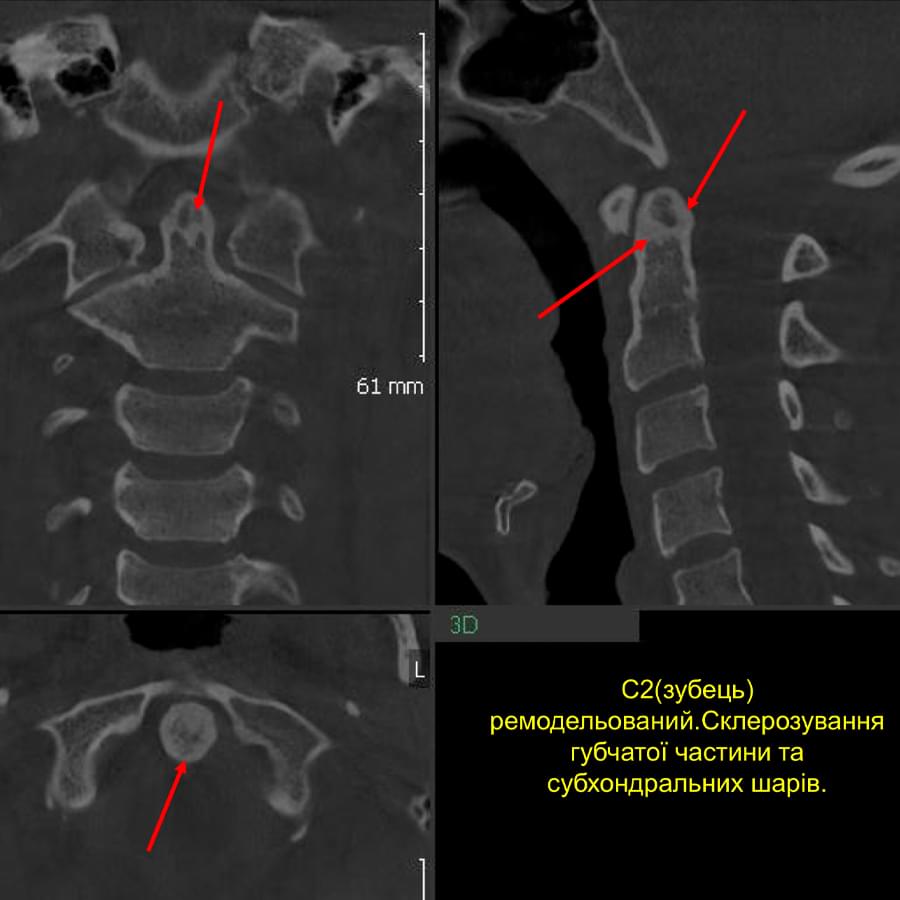

Ми розуміємо, наскільки важлива деталізація в ендодонтії та терапевтичному лікуванні.

Завдяки флагманському обладнанню PLANMECA, ми отримуємо знімки з мінімальним рівнем шумів та

високою роздільною здатністю, що дозволяє чітко візуалізувати морфологію кореневих каналів,

приховані каріозні порожнини та стан періапікальних тканин.